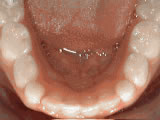

Spacing of teeth

Patient was bothered by the spaces between his teeth. Braces closed the spaces and achieved an ideal bite in 18 months. Special glued-in retainers behind he teeth help keep the spaces closed.